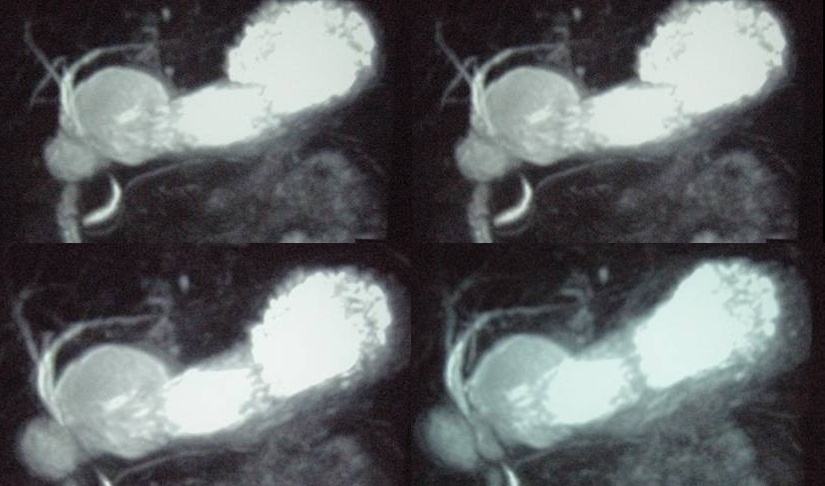

mrcp 可否再反复旋转一下角度 看看囊肿有无蒂与胆总管相连

pmrc显示病变与12指肠关系密切,与胆系不相通。

考虑十二指肠憩室。从影像上看,病变位于下腔静脉前胰头后方十二指肠内侧,肝尾叶受压,说明病变来源于后腹膜;胰胆管成像胰管和胆道未见扩张,总胆管中段受压未显示,上下段正常,所以不考虑来源与于肝尾叶和总胆管的囊肿。考虑为十二指肠憩室或小网膜囊肿。

考虑十二指肠憩室。从影像上看,病变位于下腔静脉前胰头后方十二指肠内侧,肝尾叶受压,说明病变来源于后腹膜;胰胆管成像胰管和胆道未见扩张,总胆管中段受压未显示,上下段正常,所以不考虑来源与于肝尾叶和总胆管的囊肿。考虑为十二指肠憩室或小网膜囊肿.分析的好。